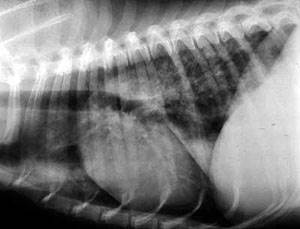

- Для определения наличия метастазов в легких проводится общий осмотр и аускультация животного, а также рентгеновский снимок грудной клетки. Учитывая, что метастазы не появляются сами по себе, а являются следствием злокачественной опухоли, проводится полная диагностика и полное обследование кошки или собаки для поиска первоначального очага онкологического заболевания и определения его типа.